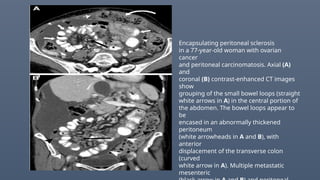

Encapsulating peritoneal sclerosis

and peritoneal carcinomatosis. Axial (A)

coronal (B) contrast-enhanced CT images

grouping of the small bowel loops (straight

white arrows in A) in the central portion of

the abdomen. The bowel loops appear to

be

encased in an abnormally thickened

peritoneum

(white arrowheads in A and B), with

anterior

displacement of the transverse colon

(curved

white arrow in A). Multiple metastatic

mesenteric

Encapsulating peritoneal sclerosis ina 77-year-old woman with ovarian cancer and peritoneal carcinomatosis. Axial (A) and coronal (B) contrast-enhanced CT images show grouping of the small bowel loops (straight white arrows in A) in the central portion of the abdomen. The bowel loops appear to be encased in an abnormally thickened peritoneum (white arrowheads in A and B), with anterior displacement of the transverse colon (curved white arrow in A). Multiple metastatic mesenteric